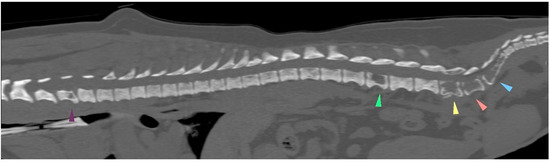

3.2. Additional Medical Tests

| 1 September 2021 | flaccid tail, evolving into posterior paresis within 24 h, spinal metastasis (CT examination) | ||||||||